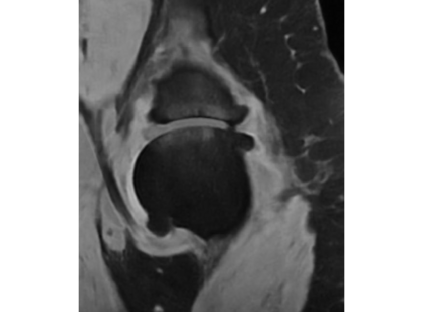

Magnetic resonance (MR) images are often acquired in 2D settings for real clinical applications. The 3D volumes reconstructed by stacking multiple 2D slices have large inter-slice spacing, resulting in lower inter-slice resolution than intra-slice resolution. Super-resolution is a powerful tool to reduce the inter-slice spacing of 3D images to facilitate subsequent visualization and computation tasks. However, most existing works train the super-resolution network at a fixed ratio, which is inconvenient in clinical scenes due to the heterogeneous parameters in MR scanning. In this paper, we propose a single super-resolution network to reduce the inter-slice spacing of MR images at an arbitrarily adjustable ratio. Specifically, we view the input image as a continuous implicit function of coordinates. The intermediate slices of different spacing ratios could be constructed according to the implicit representation up-sampled in the continuous domain. We particularly propose a novel local-aware spatial attention mechanism and long-range residual learning to boost the quality of the output image. The experimental results demonstrate the superiority of our proposed method, even compared to the models trained at a fixed ratio.